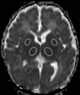

Perinatal asphyxia (also known as neonatal asphyxia or birth asphyxia) is the medical condition resulting from deprivation of oxygen to a newborn infant that lasts long enough during the birth process to cause physical harm, usually to the brain. It is also the inability to establish and sustain adequate or spontaneous respiration upon delivery of the newborn. [Source: Wikipedia ]